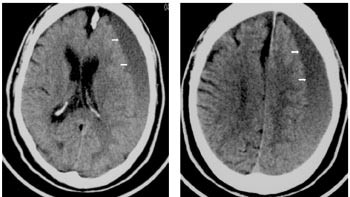

Pasienten kunne imidlertid fortelle at samboeren var sjalu og hadde gjemt danseskoene hans. Neste uke fortalte han triumferende at nå hadde han funnet danseskoene igjen og hadde gjemt dem i garderobeskapet på dagavdelingen, så nå ville han gjerne delta i dansen. Ved poliklinisk undersøkelse etter et halvt år viste CT-undersøkelsen av hjernen nærmest normale forhold (fig 3).